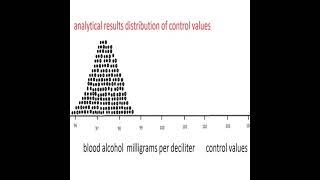

The appearance of carbon Dioxide in the mouth is indicative of lung failure